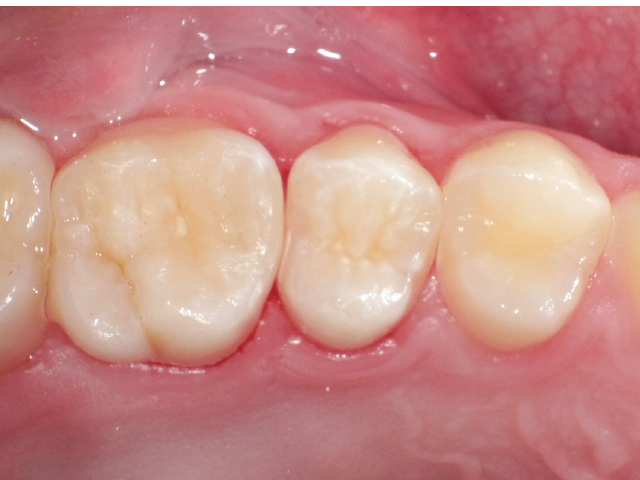

②充填段階(図10~22)

窩洞形成完了後は隣接面部健全歯質の残存範囲によりコンポジットレジンの充填時に用いるマトリックスシステムを選択していきますが、今回はシンプルな操作で設置可能なトッフルマイヤータイプのマトリックスシステムを選びました。隣在歯との距離が小さく、フラットな隣接面形態の再現が必要な症例には最適で、同時に精度の高い窩洞の防湿も可能です。使用したメタルのマトリックスバンドの厚さは30µmと非常に薄く、隣在歯との間に適切な接触関係を回復することができます。

接着操作には窩縁部エナメル質へのセレクティブエッチングに続いて、2ステップタイプのセルフエッチングシステム(クリアフィル® メガボンド®2 : クラレノリタケデンタル)を使用し、フロアブルレジンとペーストタイプレジンとを併用したシンプルな積層充填操作により隣接面形態を回復しました。